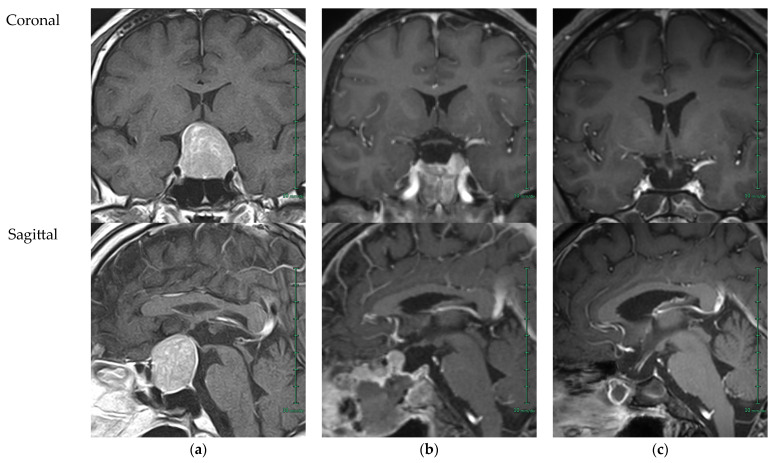

背景和临床意义:垂体腺瘤,也称为垂体神经内分泌肿瘤,在手术切除后发生促性腺功能低下(HH)的风险很大,对年轻患者的生育和性功能有深远的影响。病例介绍:我们报告一名来自日本农村的29岁男子,他在两次经蝶窦切除大垂体腺瘤后发展为严重HH和无精子症。尽管早期与神经外科团队接触,但由于缺乏现场内分泌专家和有限的当地肿瘤生育资源,生育管理被推迟。经过全面的内分泌评估和咨询,患者开始人绒毛膜促性腺激素和重组促卵泡激素联合治疗,性功能完全恢复,精液参数恢复正常,最终实现自然受孕,健康生育。基于这一真实案例,我们提供了当前垂体手术后HH的实际管理策略的叙述性回顾,包括激素刺激试验的效用,日本基于指南的补贴制度,以及激素替代的最佳实践方法。结论:该病例不仅强调了早期跨学科合作和术前咨询的必要性,而且强调了一例罕见的良性肿瘤患者接受的治疗没有解决其生育相关需求,强调了即使是非恶性肿瘤也应纳入术前咨询的考虑因素。加强区域肿瘤生育网络和提高保健提供者对保留生育选择的认识对于改善结果仍然至关重要。

Background and Clinical Significance: Pituitary adenomas, also termed pituitary neuroendocrine tumors, pose a significant risk of hypogonadotropic hypogonadism (HH) after surgical resection, with profound consequences for fertility and sexual function in young patients. Case Presentation: We present the case of a 29-year-old man from rural Japan who developed severe HH and azoospermia following two transsphenoidal resections for a large pituitary adenoma. Despite early engagement with neurosurgery teams, fertility management was delayed by the absence of on-site endocrinology expertise and limited local oncofertility resources. After comprehensive endocrine evaluation and counseling, the patient began combined human chorionic gonadotropin and recombinant follicle-stimulating hormone therapy, resulting in full recovery of sexual function and normalization of semen parameters, ultimately leading to spontaneous conception and the birth of a healthy child. Building on this real-world case, we provide a narrative review of current practical management strategies for HH after pituitary surgery, including the utility of hormone-stimulation tests, Japanese guideline-based subsidy systems, and best-practice approaches to hormonal replacement. Conclusions: This case underscores not only the necessity for early, interdisciplinary collaboration and preoperative counseling but also highlights a rare instance in which a patient with a benign tumor received care that did not address his fertility-related needs, emphasizing that such considerations should be integrated into preoperative counseling even for non-malignant conditions. Strengthening regional oncofertility networks and improving healthcare providers' awareness of fertility-preservation options remain essential for improving outcomes.